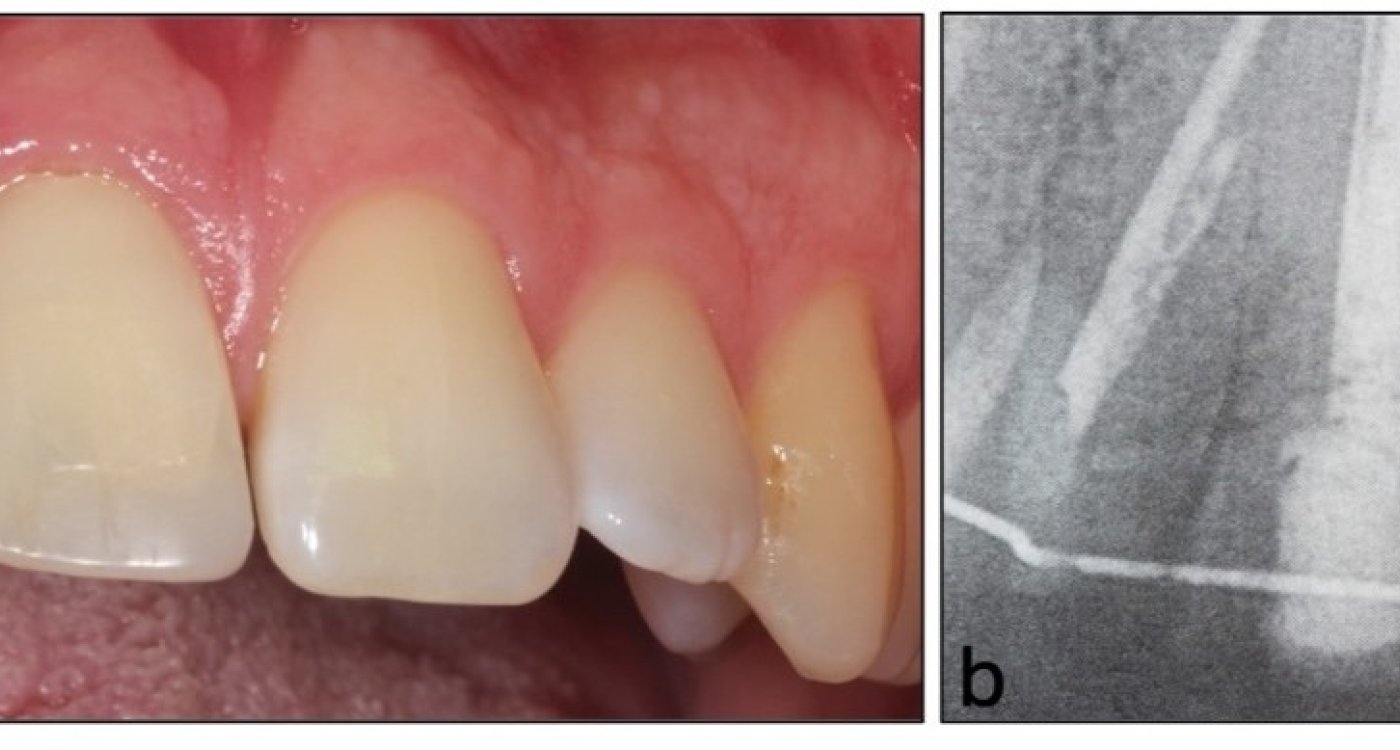

Fallstricke in der Endodontologie

Die endodontische Therapie stellt hohe Anforderungen an Diagnostik, Planung und technische Umsetzung, bietet jedoch bei leitliniengerechtem Vorgehen eine prognostisch günstige und substanzschonende Möglichkeit zum Zahnerhalt.…